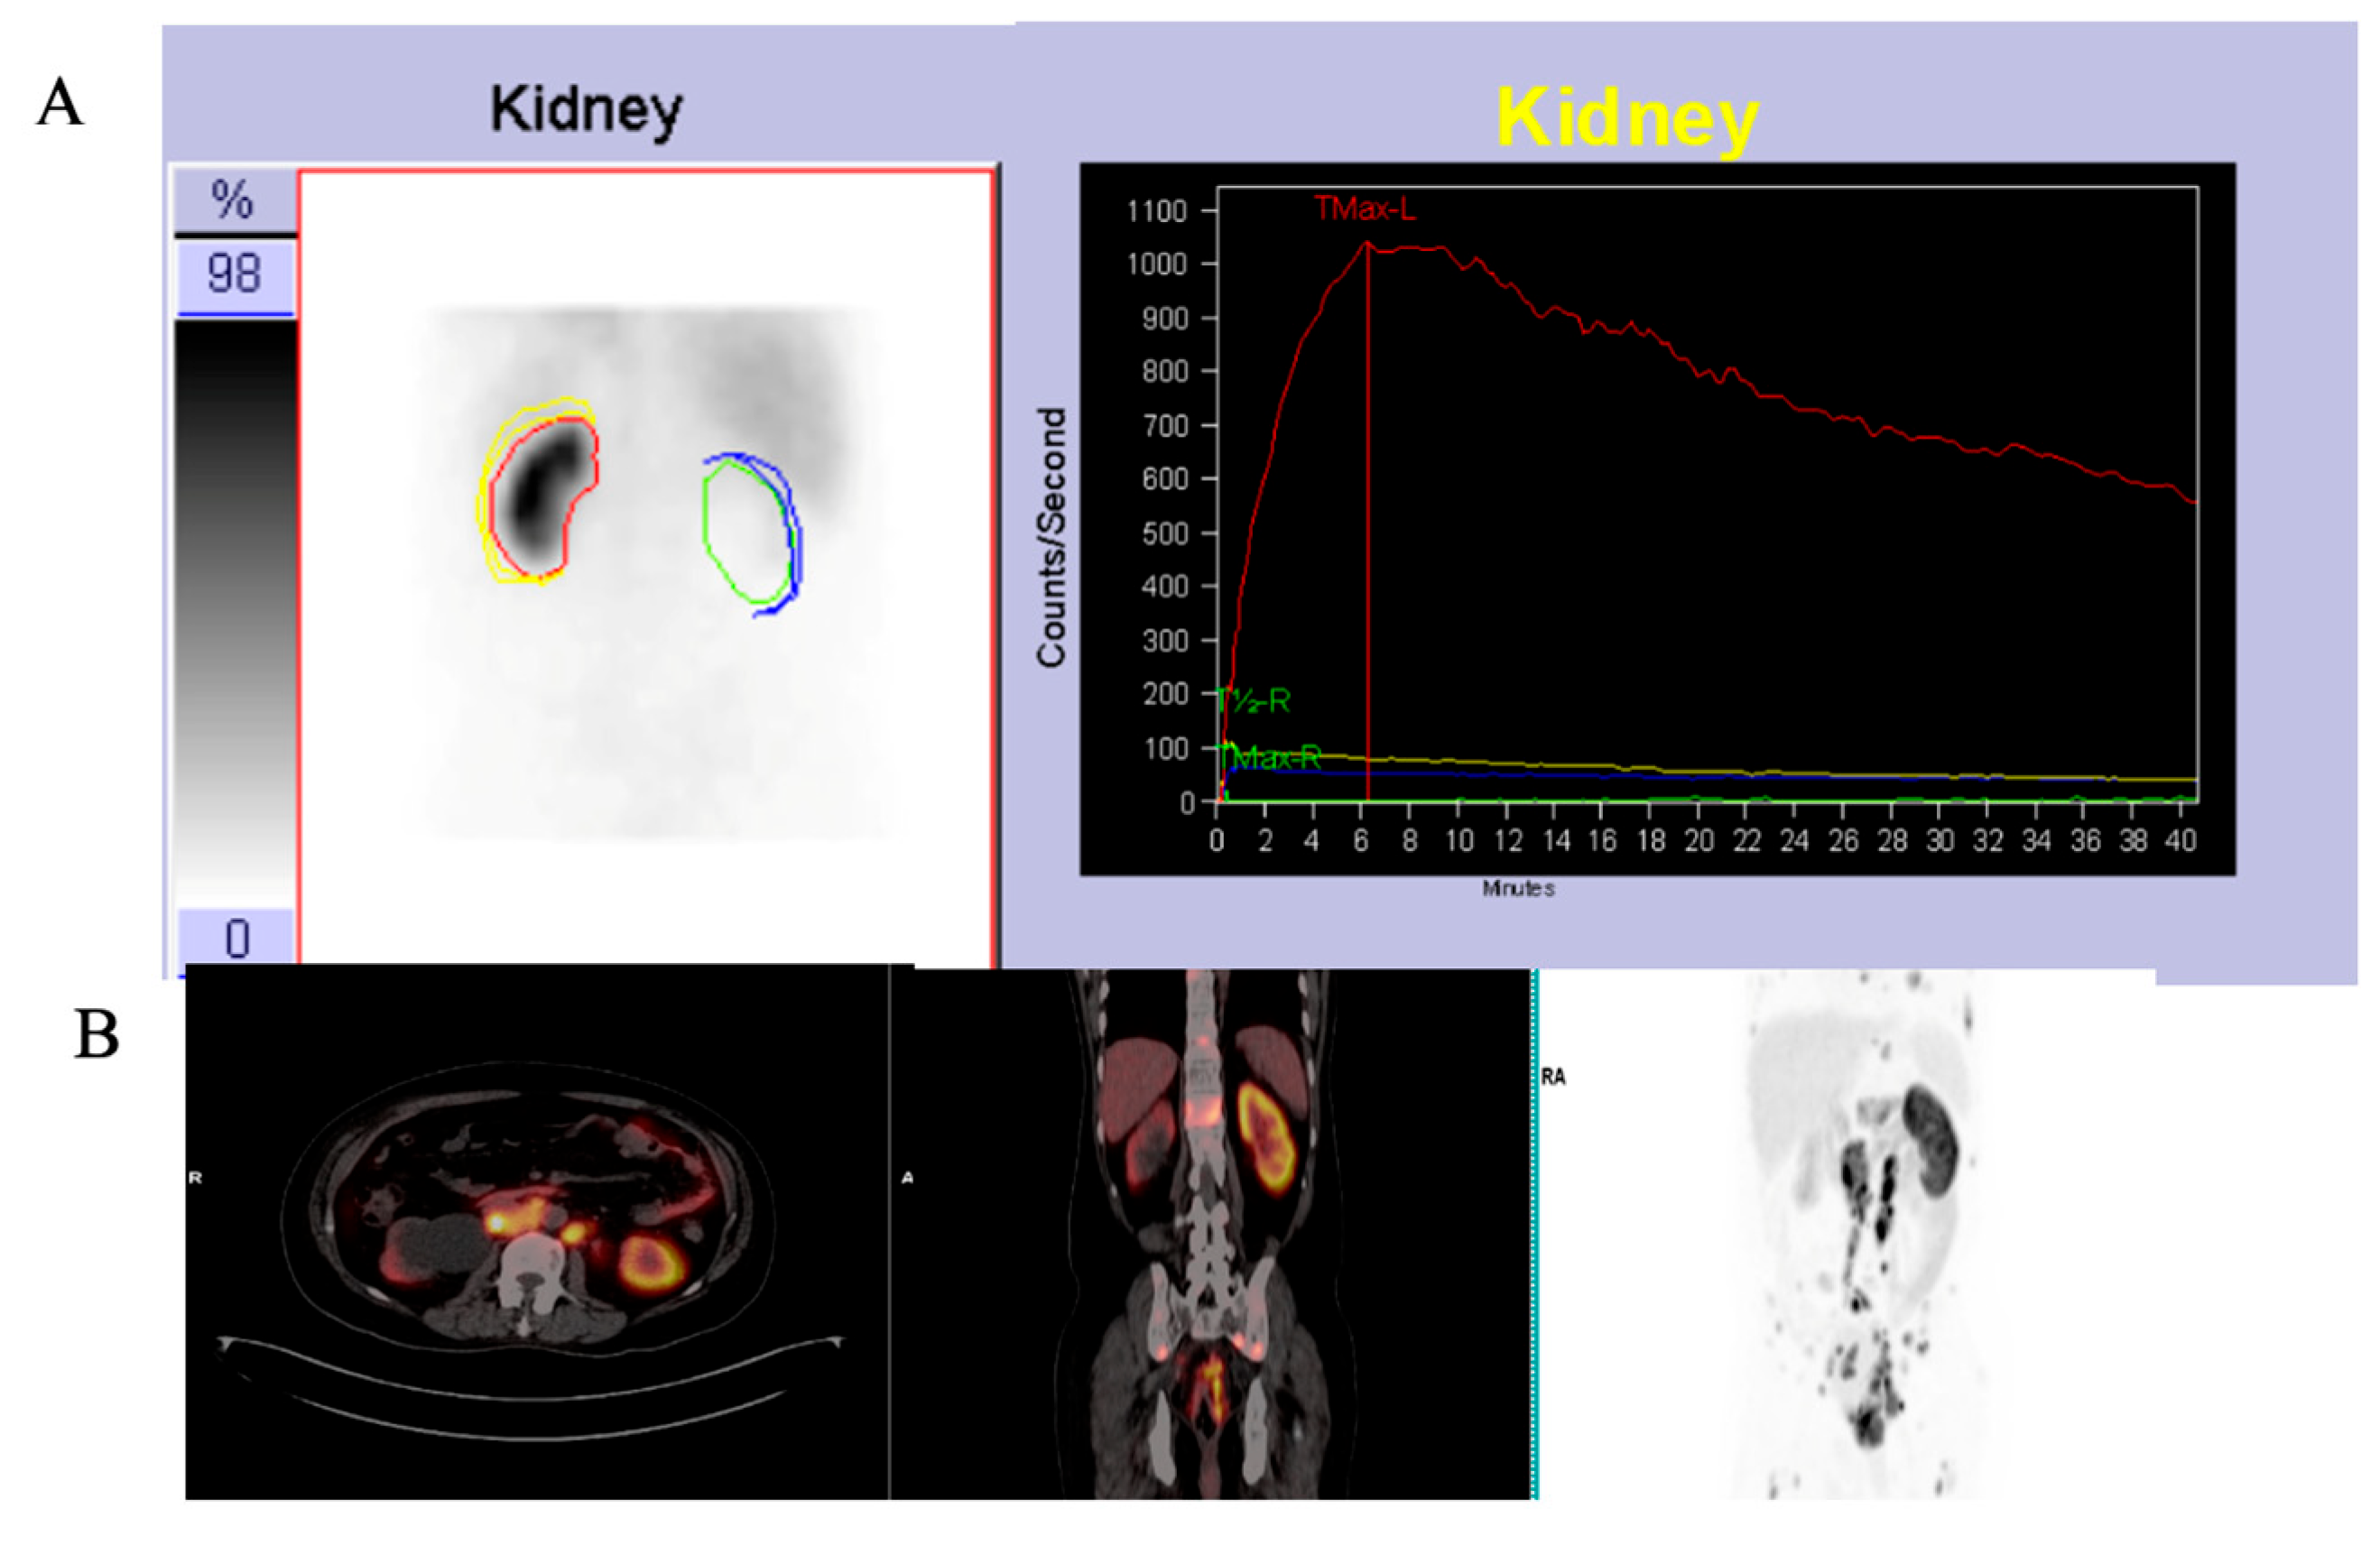

2.1.1. 68Ga-PSMA PET/CT

2.1.2. 68Ga-PSMA PET/CT Image Analysis

2.1.3. 99mTc-MAG3 Renal Scintigraphy